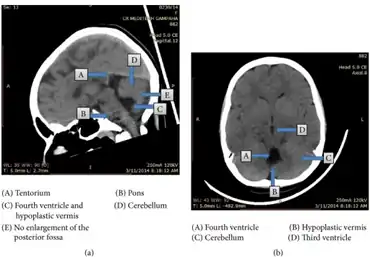

CT images of individual with Dandy-Walker malformation.

Dandy–Walker malformation is diagnosed based on the characteristic neuroimaging findings. It can be diagnosed prenatally on ultrasound as early as 14 weeks of gestation, although it is usually diagnosed postnatally by MRI. It is diagnosed within the first year of life 41% of the time, normally due to increasing signs of hydrocephalus,[18] but 28% of the time it is discovered in adolescence or adulthood due to mental health problems, such as psychosis or mood disorder.[5][6]